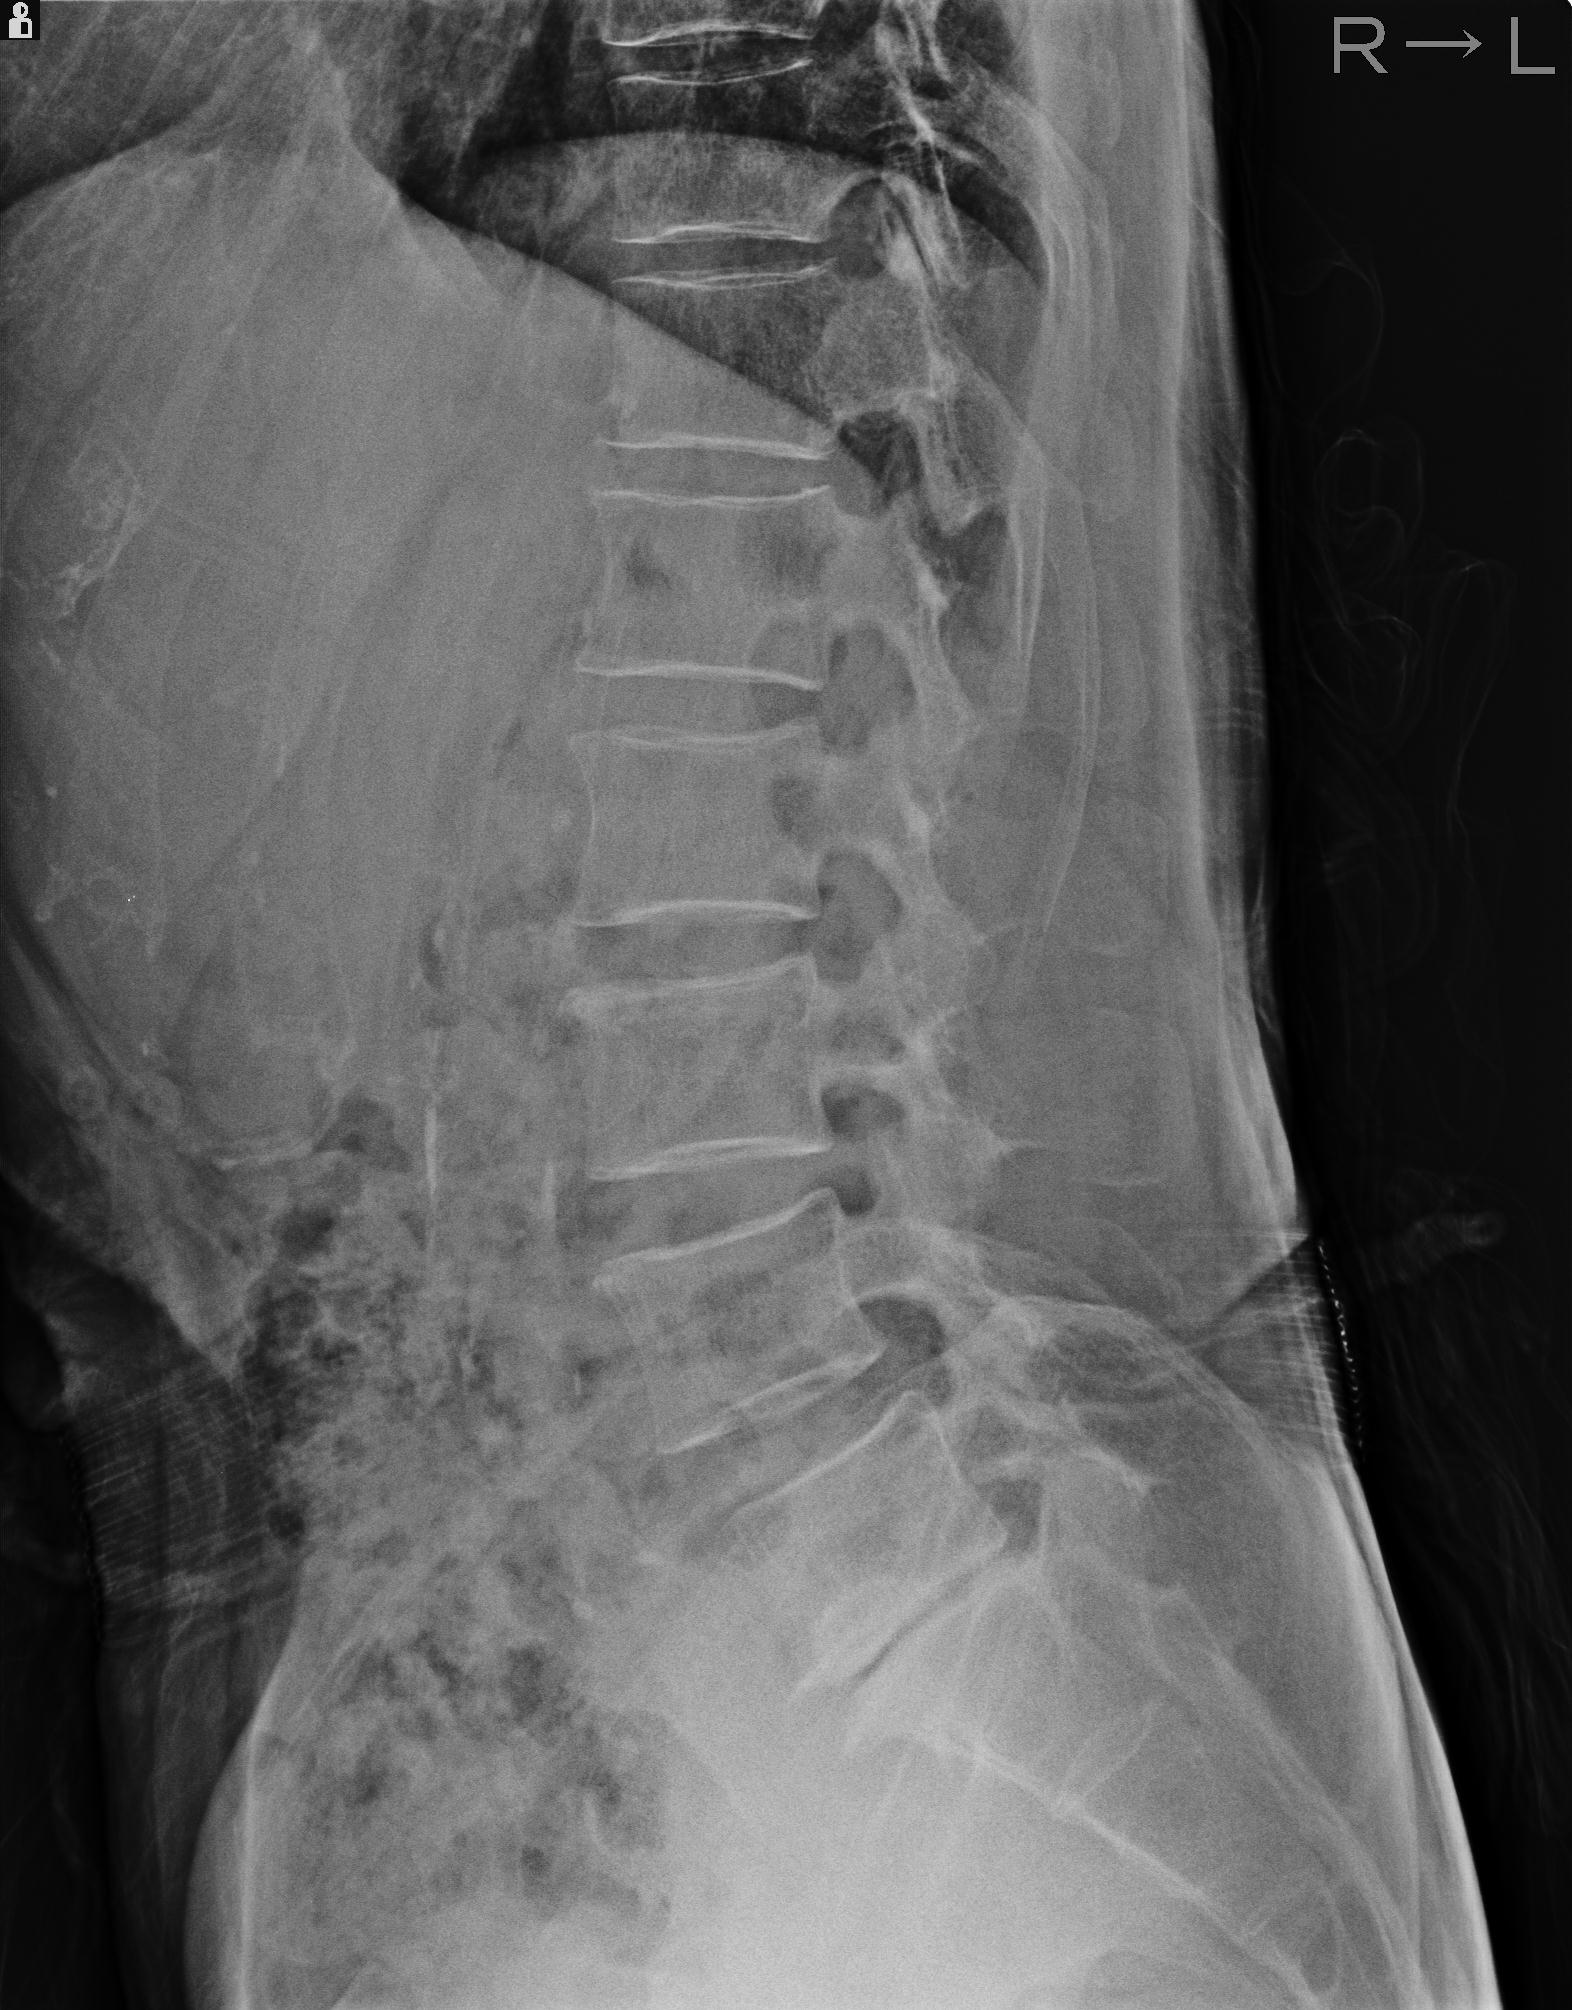

102916 2/1 と 3/22 腰椎 2R 74歳女性 LIFX